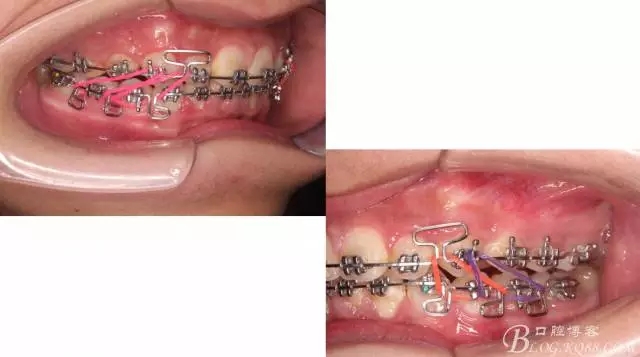

下頜配合多曲方絲,三角牽引,調(diào)整咬合。

中線不齊,咋辦?繼續(xù)哄哄患者配合,2牽+斜牽。